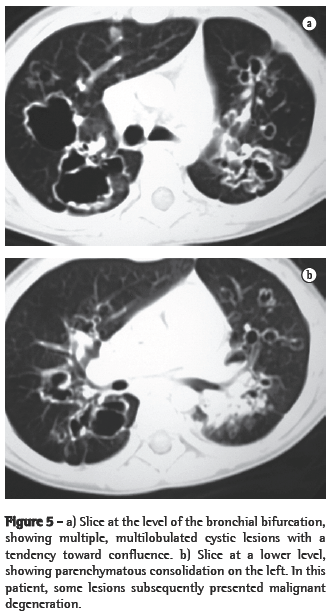

In all eight cases, the CT scans revealed polypoid formations in the trachea. In one case, injury to one of the main bronchi was identified. Seven patients presented involvement of the pulmonary parenchyma. In all eight cases, there were cavitated polypoid lesions, with irregular internal borders and walls of various thicknesses, multilobulated in six cases and presenting confluence of the lesions in five (Figures 1 through 5). Solid nodules were seen in six patients. An air-fluid level was observed in only one patient. The lesions were predominantly in the lung bases in three patients and in the middle thirds in two, whereas they were evenly distributed in two. In one patient, the lesions were accompanied by a mass, and, in another patient, they were accompanied by consolidation. In the latter case (Figure 5), there was malignant degeneration in multiple lesions. Signs of air trapping were also observed in one case. There were no identified instances of lymph node enlargement or pleural effusion.

Chest X-rays are inferior to CT scans of the chest, especially those performed using spiral CT (volumetric acquisition), in the initial phases of pulmonary dissemination, due to the fact that CT better characterizes and allows better visualization of nodular tracheobronchial vegetation, Tomographic findings include focal or diffuse airway narrowing caused by the nodules. The nodules form on the mucosal surface, and their invasion into the lumen is best evaluated using CT.(3) These alterations are easily correlated with the disease when there is a clinical history of papillomatosis.(4) Other findings related to airway obstruction and accompanying infections are atelectasis, consolidations, air trapping and bronchiectasis.(2-4) In our sample, polypoid formations in the trachea were observed on all of the CT scans Seven patients presented involvement of the pulmonary parenchyma, characterized by cavitated polypoid lesions with irregular internal borders and walls of various thicknesses, with a multilobulated aspect and a tendency toward confluence. Solid nodules were seen in six patients. None of the patients presented lymph node enlargement or pleural effusion.

Malignant degeneration to squamous cell carcinoma is reported in 1% to 10% of all cases of laryngotracheobronchial papillomatosis,(3,4) typically occurring after radiotherapy or chemotherapy with bleomycin, as well as in patients with a history of smoking.(1,6) It can occur in childhood or even decades after the diagnosis of benign papillomas.­(4) In most cases, it occurs in patients having previously presented dissemination of the disease to the tracheobronchial tree. Malignant degeneration rarely occurs in patients with the laryngeal form of the disease.(2,5) In one of the cases evaluated here, there was malignant degeneration reported based on biopsy findings in three different lesions.